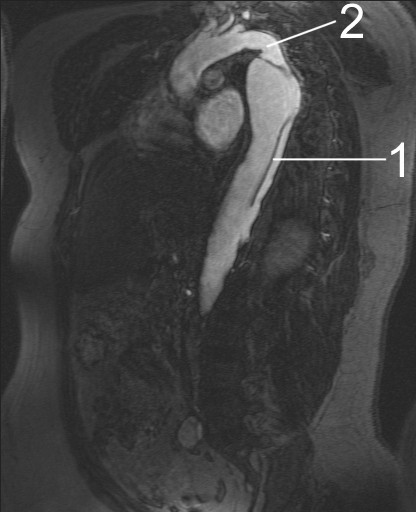

Aortic Dissection

Aortic dissection is caused by shearing force allowing blood leaking through the media of the aortic wall due to an intimal tear.

Aortic dissection occurs in the high-stress zone of the proximal portion of the aorta and is accompanied by medial weakening.

Risk factors of aortic dissection include:

- Hypertension in elderly persons, characterized by vasa vasorum hyaline arteriosclerosis

- Genetic connective tissue abnormalities in younger individuals such as Marfan syndrome or Ehlers-Danlos syndrome, characterized by weak connective tissue and cystic medial degeneration

The media sags as a result of decreased flow.

Weakness of the connective tissue in the media is a characteristic symptom of Marfan syndrome and Ehlers-Danlos syndrome (cystic medial necrosis).

Symptoms of aortic dissection include:

- Intense chest pain

- Chest pain that radiates to the back

Complications of aortic dissection include:

- Death secondary to cardiac tamponade (the most common)

- Rupture with lethal hemorrhage

- Obstruction of branching arteries (such as the coronary or renal arteries)

- End-organ ischemia